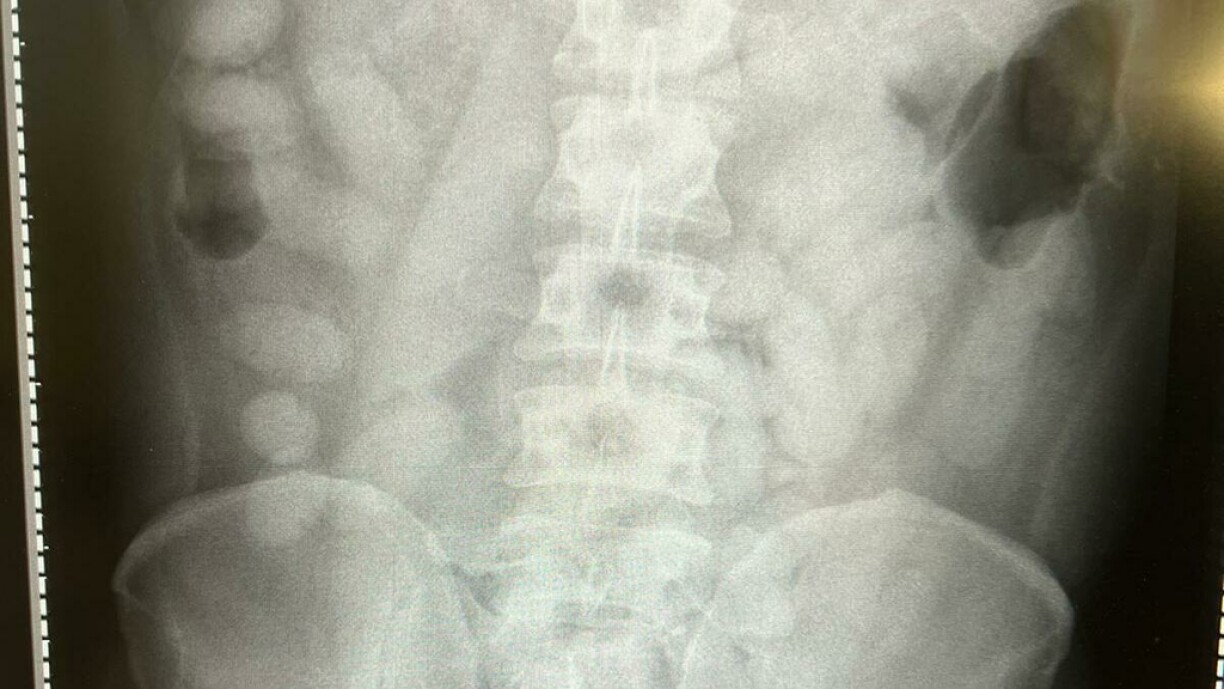

La police a alors procédé à un test de dépistage de drogue sur ses mains et y a trouvé des restes de cocaïne.“Une radiographie dans un hôpital voisin a confirmé ensuite les soupçons. Tout l’appareil digestif de l’homme était rempli de boulettes de drogue, aussi appelées body packs”, selon un porte-parole de l’administration des douanes.

Au total, les douaniers ont trouvé 72 boulettes que la mule avait avalées. Chaque boulette contenait 14 grammes de cocaïne. “Avec plus d’un kilo de cocaïne dans le corps, c’est pour nous, un nouveau triste record”, d’après le porte-parole. Si une seule des 72 boulettes qu’avait ingurgitées l’homme, s’était ouverte, il aurait couru un risque mortel.